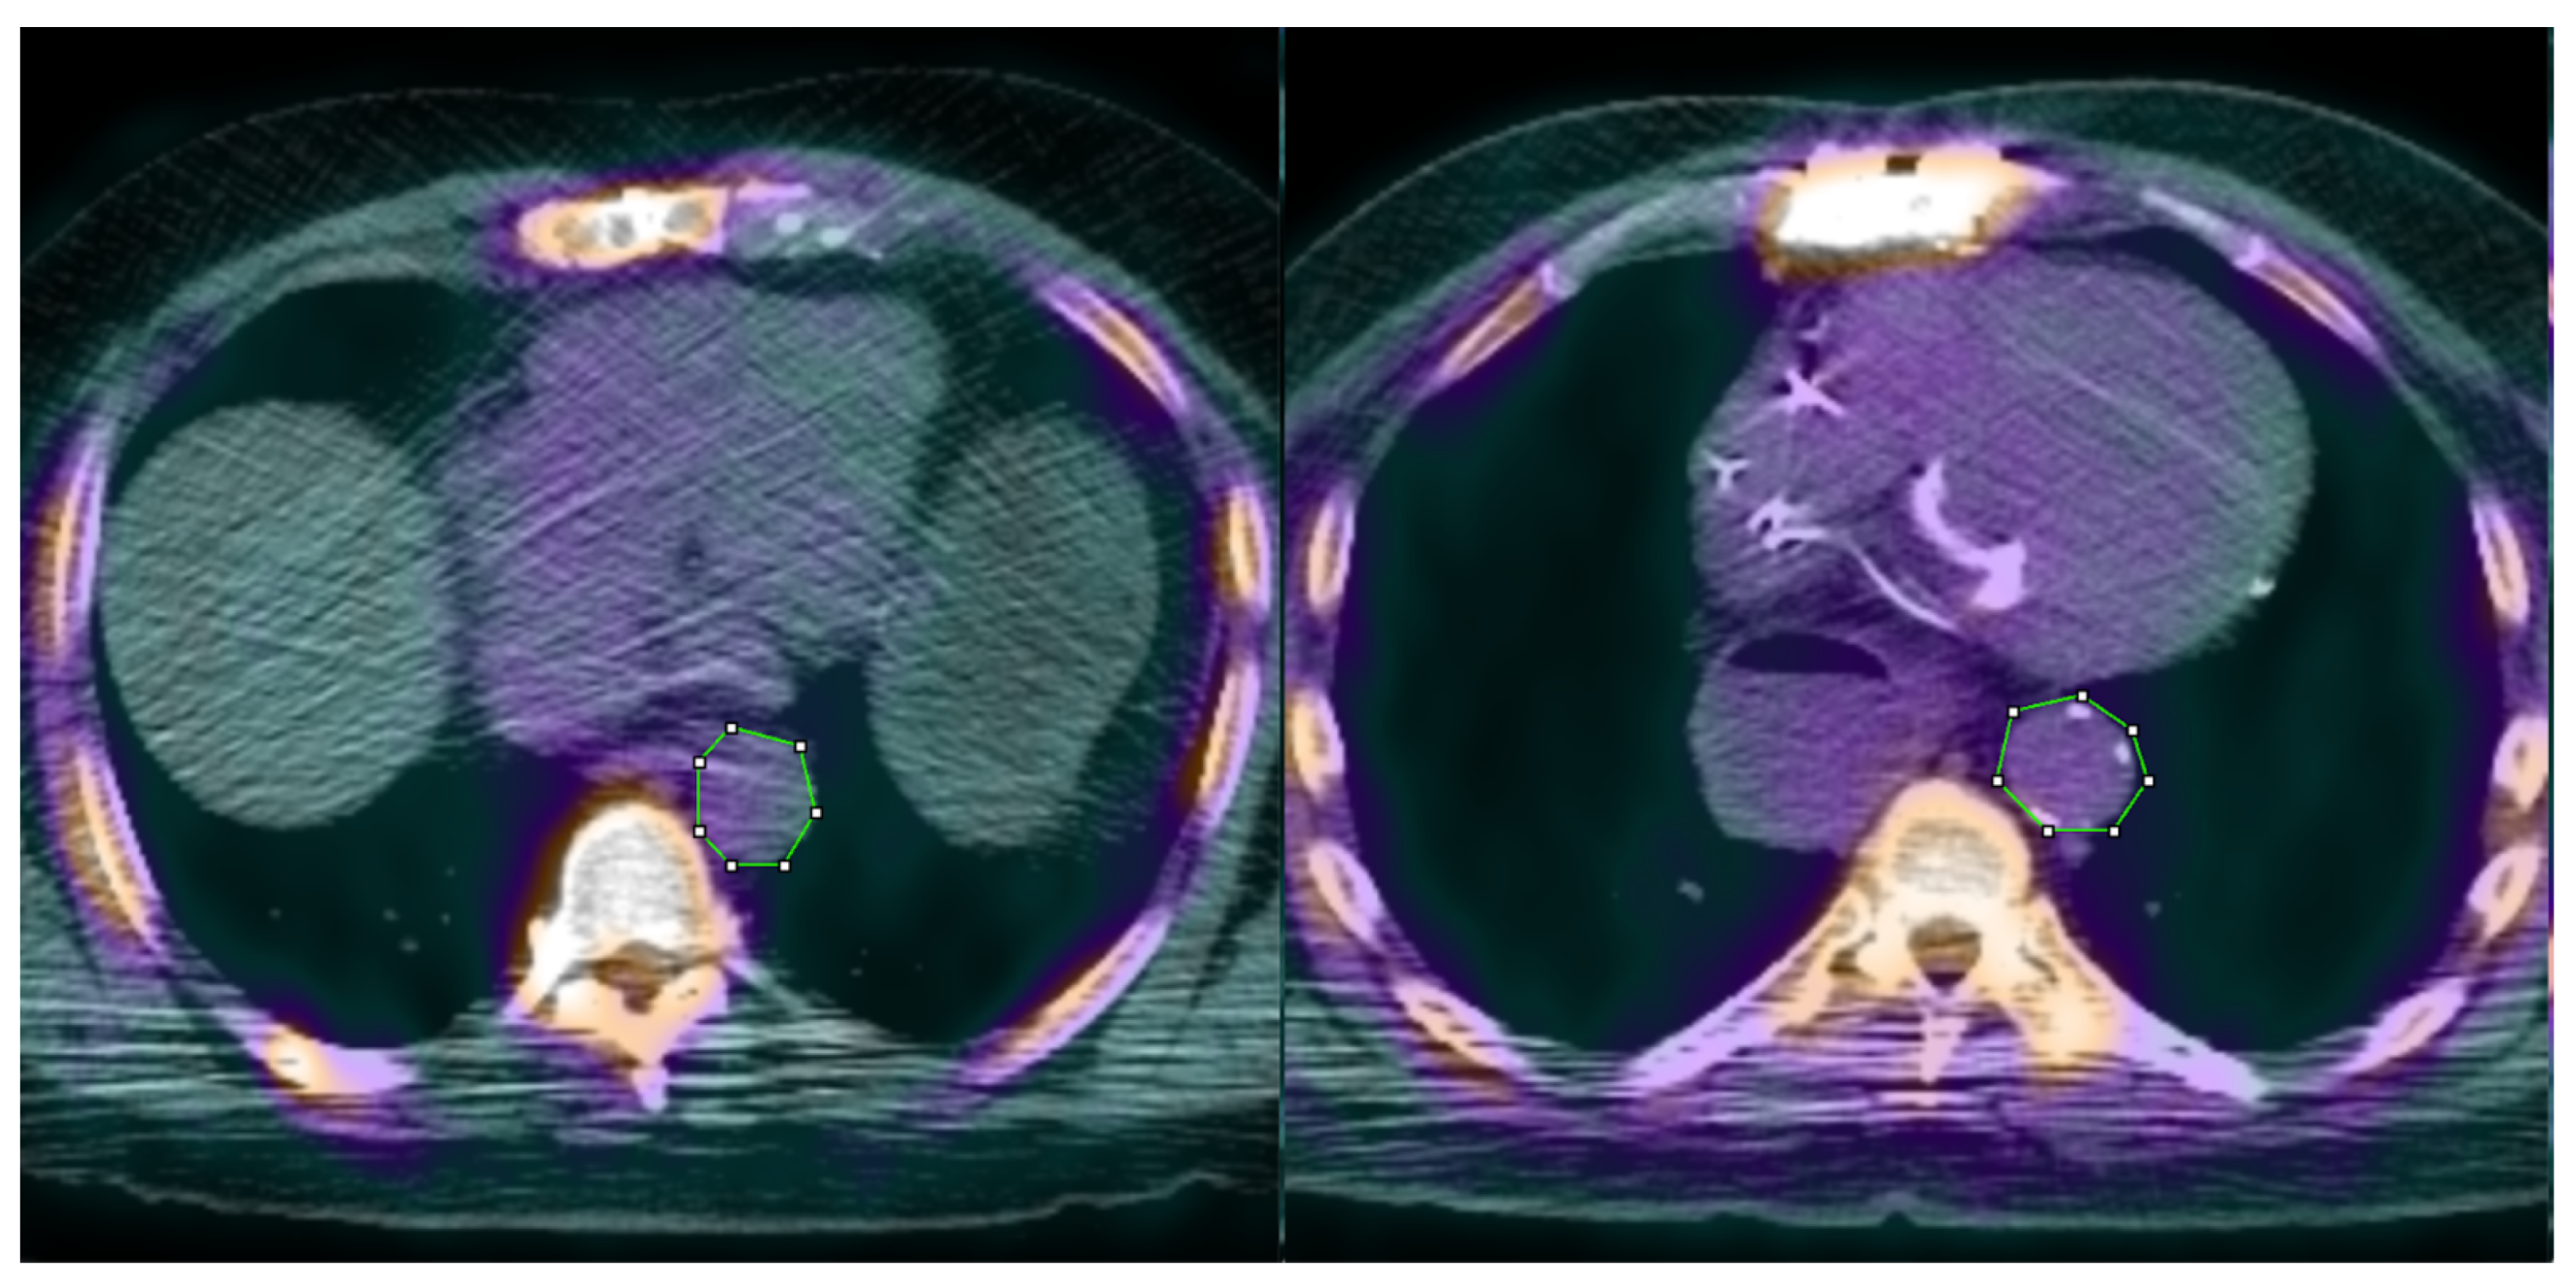

| Left | Right | |

|---|---|---|

| Age (years) | 68 | 71 |

| Weight (kg) | 100.2 | 99.3 |

| Height (m) | 1.83 | 1.77 |

| BMI (kg/m2) | 29.97 | 31.42 |

| 18F-NaF dose (mCi) | 9.8 | 10.4 |

| CRI-I | 3.08 | 4.74 |

| CRI-II | 1.65 | 3.31 |

| AC | 2.08 | 3.74 |

| AIP | 0.33 | 0.62 |

| HDL (mg/dL) | 51 | 35 |

| Aortic SUVmean | 1.285 | 1.495 |